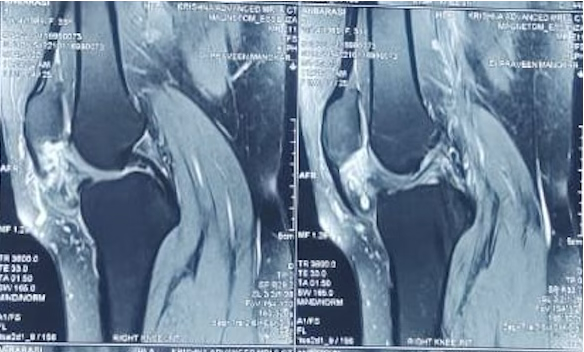

A 35-year-old female presented to the orthopedic outpatient department with a 3-year history of persistent anterior knee swelling and pain affecting her right knee. She denied any major inciting trauma, although she recalled a minor fall in adolescence, which she believed was unrelated. Over time, the swelling gradually increased in size, and her discomfort worsened with knee flexion or prolonged weight bearing. She had no constitutional symptoms such as fever, weight loss, or malaise. Her past medical history was unremarkable, and there was no significant family history of vascular malformations. On examination, the patient lay supine with neutral alignment of the lower limbs. A palpable swelling measuring approximately 5 cm × 4 cm was observed in the infrapatellar region just medial to the patellar tendon. There were no signs of skin discoloration, venous prominence, or sinus formation. Palpation elicited mild tenderness; however, there was no local rise in temperature. Knee flexion was possible from 0° to 130° with discomfort at the terminal arc, exacerbated by deep flexion. Initial plain radiographs showed a non-specific soft-tissue prominence in the same area without evidence of bony involvement or calcifications. An MRI of the right knee revealed a lobulated lesion in Hoffa’s fat pad measuring about 4.8 cm × 2.6 cm × 4.9 cm, hyperintense on T2-weighted sequences and displaying septations consistent with vascular channels. No extension into bone or joint cartilage was evident, and there were no features suggesting aggressive infiltration. Based on these findings, a vascular malformation-likely a cavernous hemangioma-was suspected. The patient was counseled regarding the need for surgical excision to alleviate symptoms and confirm the diagnosis. After pre-operative clearance and standard laboratory work-up, she underwent surgery under spinal anesthesia with a pneumatic tourniquet applied to the thigh. An anteromedial longitudinal incision was made over the infrapatellar area. Careful dissection revealed a well-defined vascular mass within Hoffa’s fat pad. En bloc resection was performed, ensuring clear margins. Hemostasis was secured, and the wound was closed in layers with a drain in place (Figs. 1, 2).

Figure 2: Sagittal T2 weighted magnetic resonance imaging shows loculated heterogenous lesion in in Hoffa’s fat pad right knee.